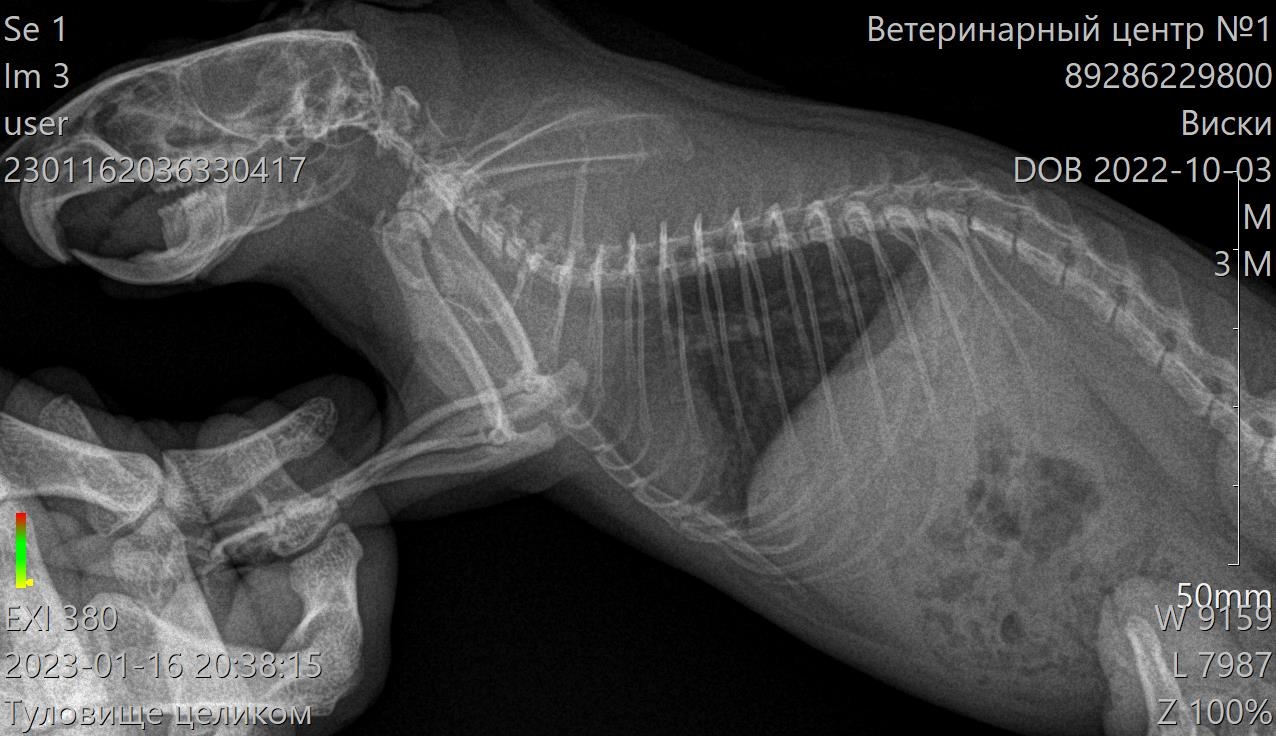

Вообще, если получится сделать ей рентген в обычной ветклинике(голову в прямой и боковой проекции), то пришли сюда снимки - там они в клинике не разберутся, но я гляну. Если сам не пойму, попытаюсь связаться со своей клиникой - вдруг там что-то сидит.